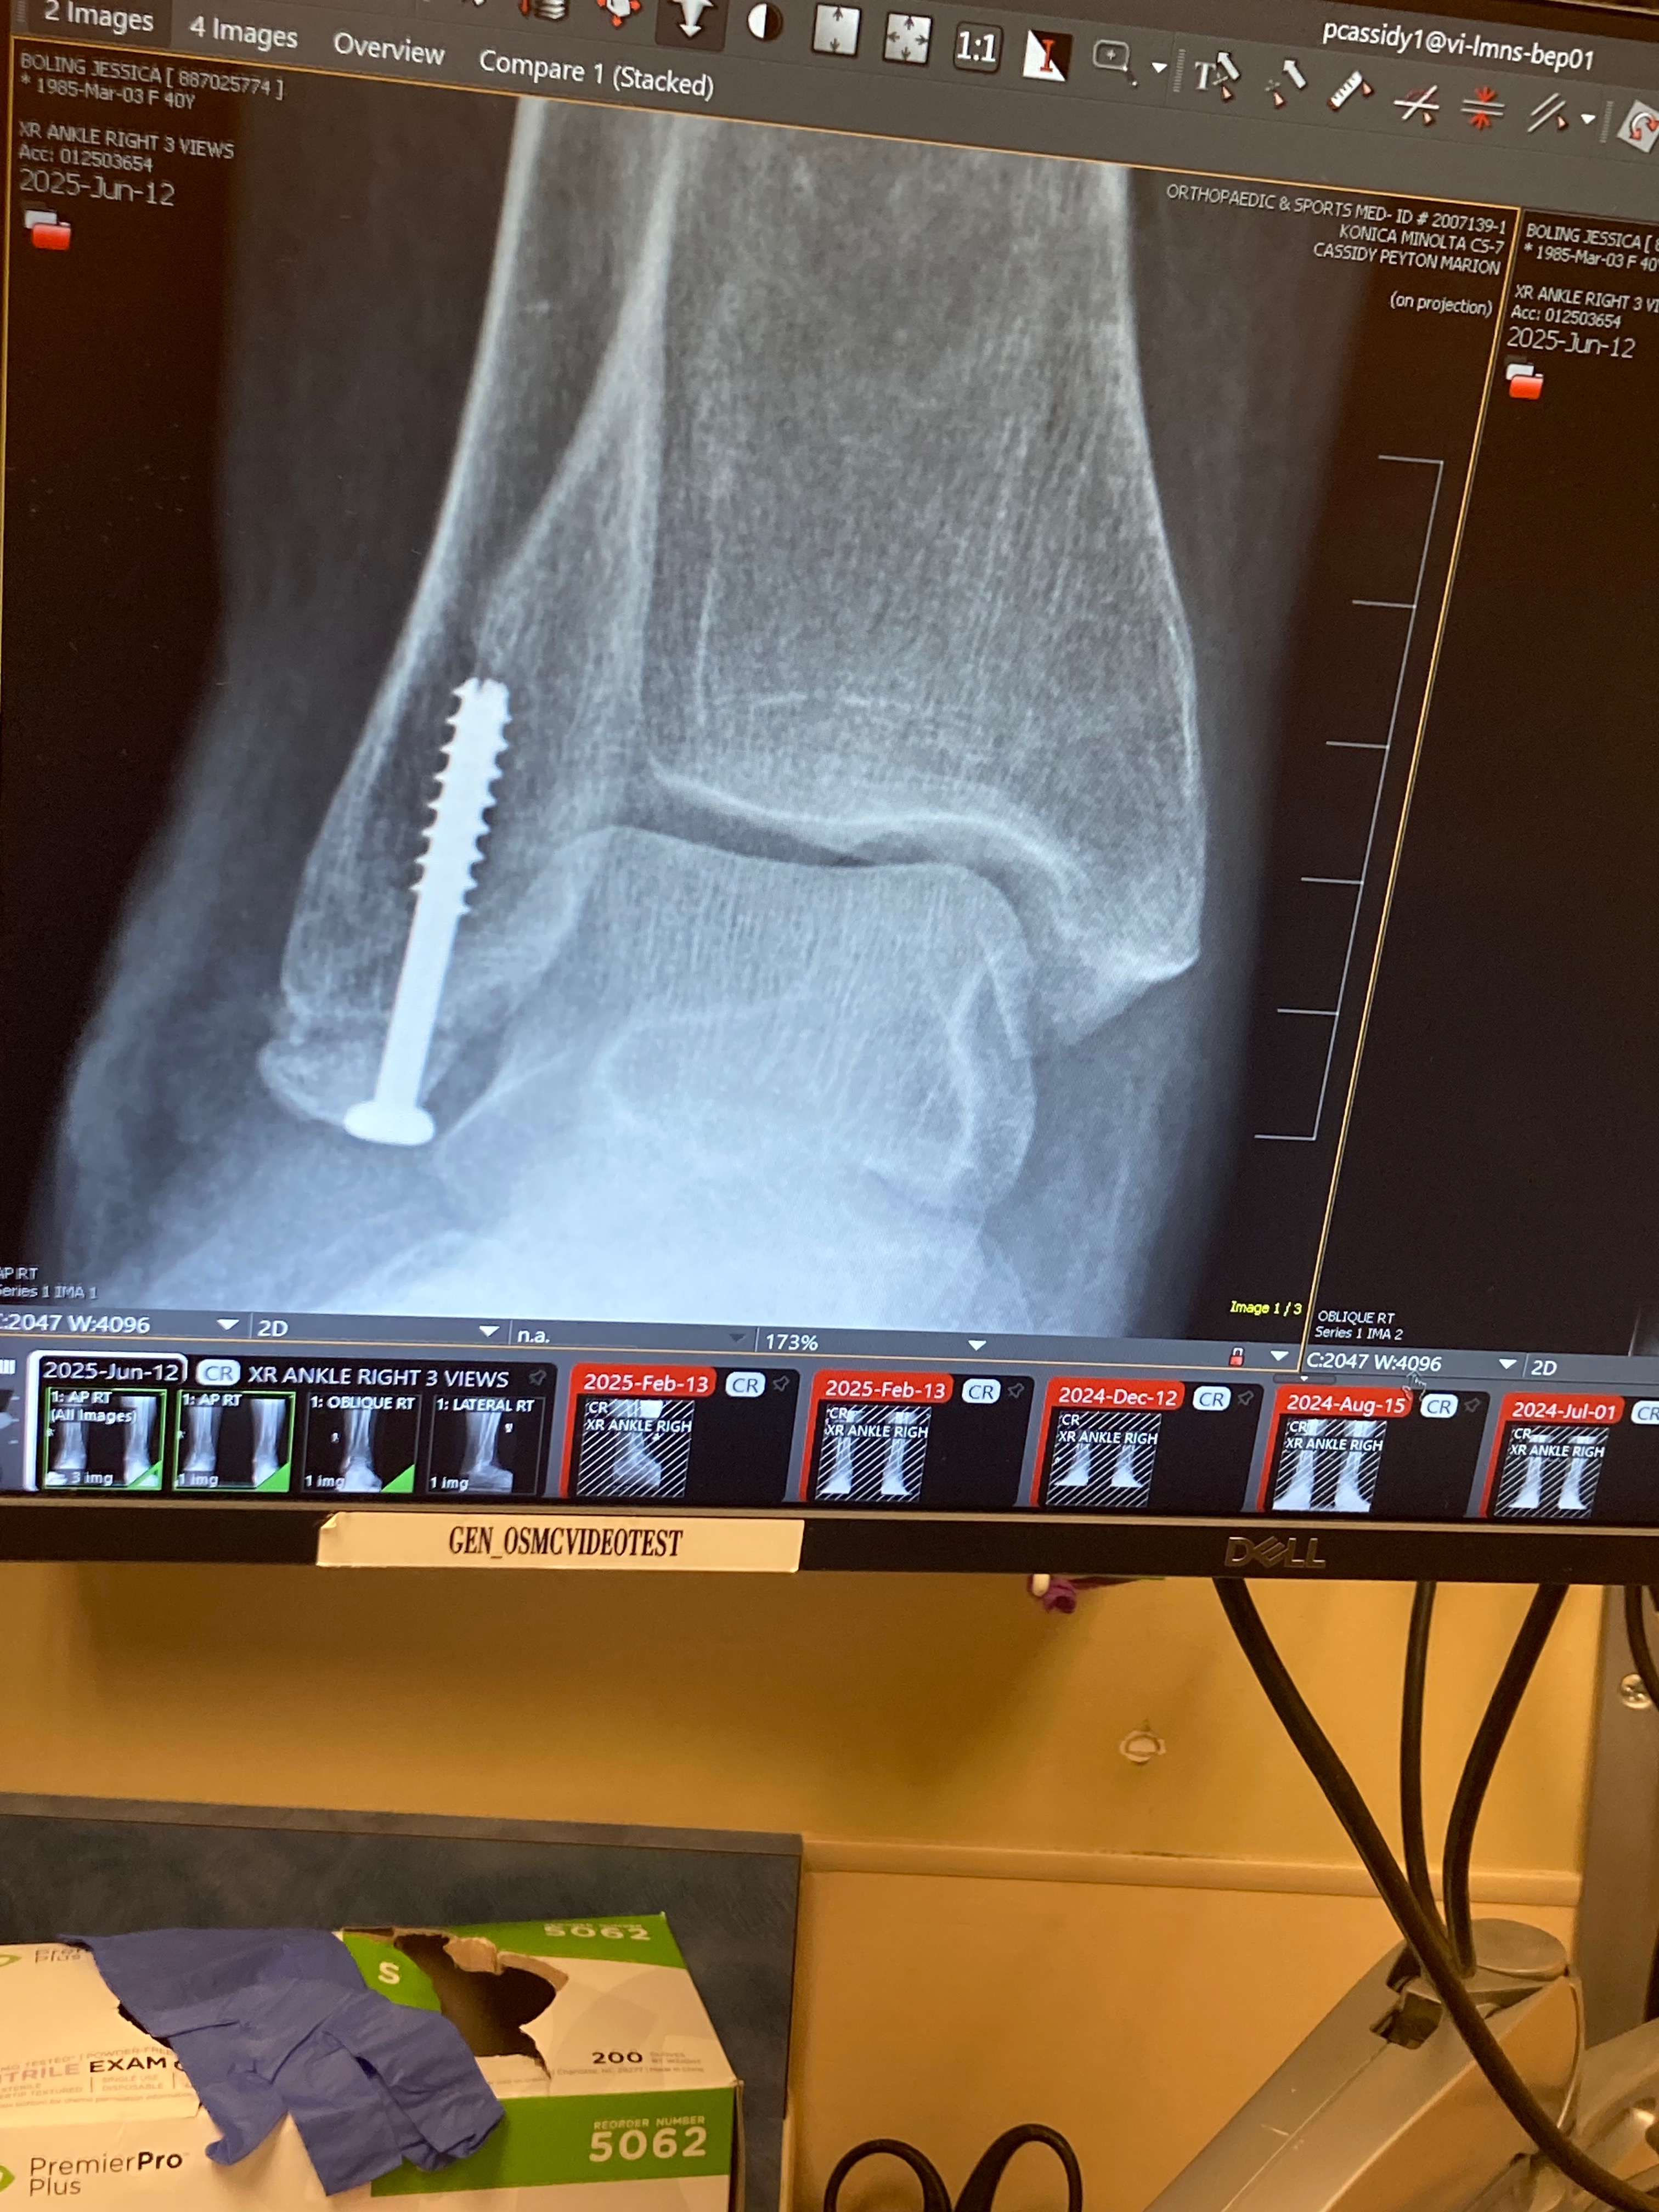

Hi, my name is Jess. I’ve been a veterinary technician for 21 years up until recently when I could no longer perform at my best ability due to breaking my ankle back in April of 2024. Still, I push my body day in and day out, literally walking about on a broken ankle. After a year of not an ounce of healing, my doctor decided to do surgery then. Needless to say, I haven’t been able to work. I’ve fallen into a deep depression because my job was my life, the animals my purpose, and now it’s gone. I have 80 cents to my name, so I can’t pay the bills. I’m filing for disability, which can take a while, which is why I’m asking for help. Even the smallest donation will make a huge difference.